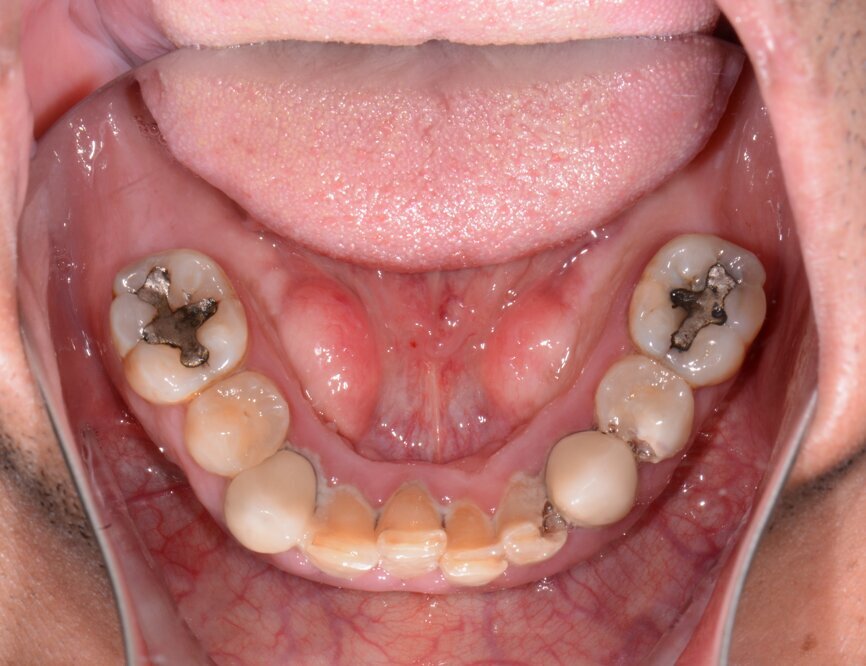

A patient presented to my practice for a consultation wanting to restore his dentition to proper form and function (Fig. 1). He complained of generalised discomfort due to the gross caries and periodontal disease that was readily apparent (Figs. 2 & 3). There were several teeth in both arches that had so much extensive decay that only the root tips were apparent upon clinical examination. Also, there was hyper-eruption in certain areas of his posterior dentition, as well as a deep impinging bite in the anterior.

Fig. 3: Pre-op mandibular occlusal view.